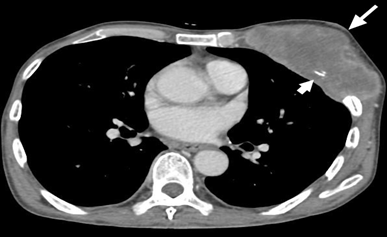

Figure 3 CT scan image axial view showing a lobulated, heterogeneous enhancing mass occupying the whole left breast (white arrow) with infiltration into the left Pectoralis major and minor muscle and erosion of the adjacent ribs (short arrow).